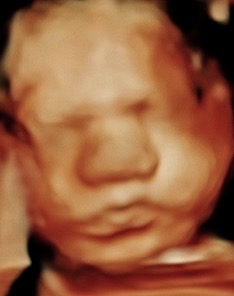

Hi, my name is Crystal Heller, and I’m the owner of Miracle 3D Moments. For the past five years, I’ve had the privilege of helping moms, dads, and families see and bond with their babies before they’re born. It’s been the most rewarding part of my life watching the smiles, the tears of joy, and the comfort that comes when a mom-to-be sees her little one moving, yawning, and even smiling.